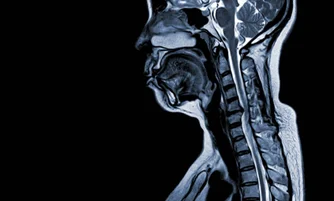

Spinal problems can affect much more than the back, impacting daily activities, sleep, and overall quality of life. Persistent pain, stiffness, or nerve-related symptoms should be addressed early to avoid long-term complications.

Dr. Naveen Tahasildar, a leading Spine Surgeon in Bangalore, offers advanced, evidence-based treatment for disc disorders, nerve compression, spinal deformities, tumors, and minimally invasive spine procedures—focused on restoring mobility, strength, and a pain-free, active life.